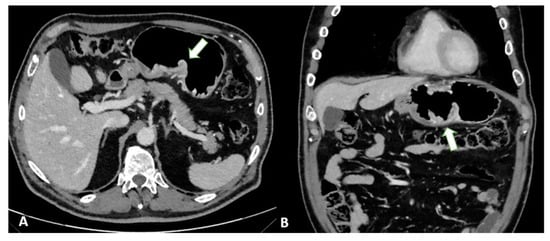

Advances in imaging techniques, such as the introduction of diffusion-weighted imaging (DWI), may provide important data for the definitive diagnosis of various pathologic entities. In this context, DWI can help to distinguish T4 from the lower stages of GC with a high reliability [49]. The authors reported a sensitivity of 92.1%, specificity of 75%, and accuracy of 89.1% for ≤T2 vs. ≥T3 lesions and a sensitivity of 75%, specificity of 88.5%, and accuracy of 82.6% for ≤T3 vs. T4 lesions in 46 patients (Figure 9).

Figure 9.

MRI images of a T3 gastric cancer of the gastric antrum in a 79-year-old male patient. (A) Coronal 2D image and (C) Axial 2D image of the Turbo Spin Echo (TSE) T2 sequence showing a circumferential lesion (arrow) invading the subserosa layer with an intermediate signal intensity; (B) Coronal 2D Balance Fast Field Echo (BFFE) sequence showing a circumferential lesion (arrow) with a low signal intensity; (D) Axial Diffusion Weighted Image (DWI) showing an area of signal restriction (arrow) corresponding to the tumor.